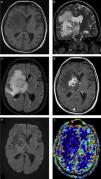

Si bien su rol en la evaluación de accidentes cerebrovasculares o tumores del sistema nervioso ha sido bien establecido, es una herramienta de particular interés en el paciente con infección37. Debido a la constitución de la cápsula de los AC, rica en colágeno y poco vascularizada, es fácil distinguir estas lesiones de los tumores que pueden presentarse de forma similar en las secuencias convencionales38,39. Así, en la PWI se muestran valores bajos del VSC, sin alteraciones de la permeabilidad en la zona de máximo realce (o sea, en la cápsula de la lesión)39(fig. 10). En el caso de los valores de VSC encontrados en el centro necrótico de los tumores y los AC, estos no tienen diferencias significativas, por lo que es necesario un correcto análisis de los distintos sectores de la lesión40.

Abscesos cerebrales bacterianos: comportamiento en la perfusión. La RM en las secuencias seleccionadas, en los 2 pacientes con AC bacterianos confirmados luego de su evacuación quirúrgica, presenta (a y d) el clásico fenómeno de restricción en la difusión y (b y e) un mapa de ADC con (c y f) valores bajos de volumen sanguíneo cerebral en la perfusión.

La PWI constituye una herramienta eficaz en la diferenciación entre los AC y los tumores necróticos, que -como mencionamos anteriormente- en alguna circunstancia pueden presentar restricción en el centro. Chan et al. han demostrado que los valores de VSC relativo (rVSC) en la pared de diferentes tumores quísticos o necróticos son superiores a los de la sustancia blanca normal, en comparación con los de la pared de los AC41.

La técnica de perfusión puede ser utilizada en todas las ISN, ya que por norma general se trata siempre de lesiones con bajo VSC, es decir, hipoperfundidas (figs. 7 y 9).